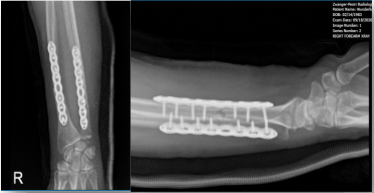

Right Forearm X-ray-16th week post-operative